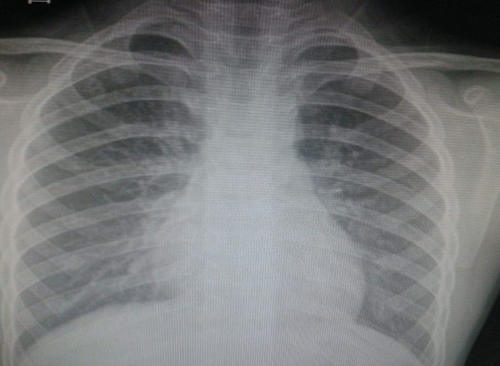

第四项就是心电图,这是对心脏最直接且最有效的检测。而血压经常升高的患者,最不能漏掉的就是心电图。第五项就是胸片,由于一般会让检测者站在黑屋子中,且须站在机器中间,造成很多人的抗拒。大多数人认为这对身体有害,毕竟是X光,照一下对身体可能对身体不好。可这其实是谣言,胸透能直接检测人体肺结构是否有炎症,且比较经济实惠。科学方面来讲,必要的激光照射对人体也是一件好事,更何况是对疾病有所治疗的。